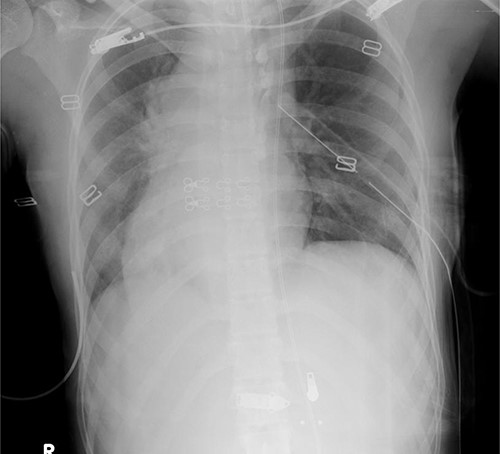

On examination, she was hypotensive (blood pressure, 60 mmHg; heart rate, 110 bpm) with a Glasgow Coma Scale score of 6 (E1V2M3), and she responded to fluid resuscitation. A chest radiograph showed a right-sided heart, indicating dextrocardia and widening of the upper mediastinum (Fig. 1).

Chest radiograph showing a right-sided heart and widening of the upper mediastinum.